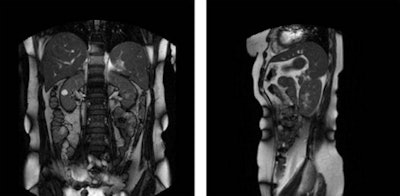

The capability of providing MRI during the irradiation process will allow radiation therapists to monitor the position of a tumor with real-time imaging and adapt the treatment to the patient, according to the authors. To determine the stability and reproducibility of the kidney position, the research team recruited 15 patients with renal lesions to be imaged while using two breathing techniques.

Both sagittal and coronal dynamic scans of the kidney were acquired during free breathing. Stam and colleagues determined the mean and standard deviation of the expiration peaks after they were determined. They also created a linear fit of the kidney positions during expiration, and these calculations helped the research team determine the reproducibility of the kidney position.